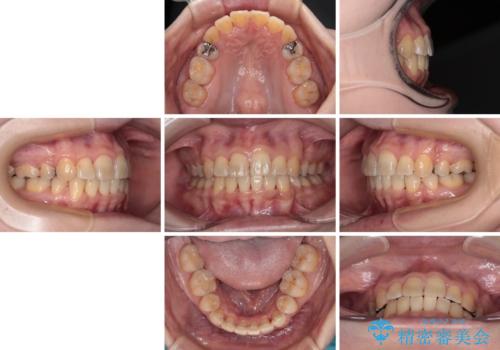

後戻りにリカバリーに少し時間を要しましたが、1年強の期間で無事に治療を終えることができました。

- 海外で抜歯矯正を開始し、治療途中で帰国したため、転院先を探しているとのことで来院された患者様です。

当院では、張り替える必要のある部位は張り替えることで継続することとし、抜歯スペースを閉じていくように治療を行うこととしました。